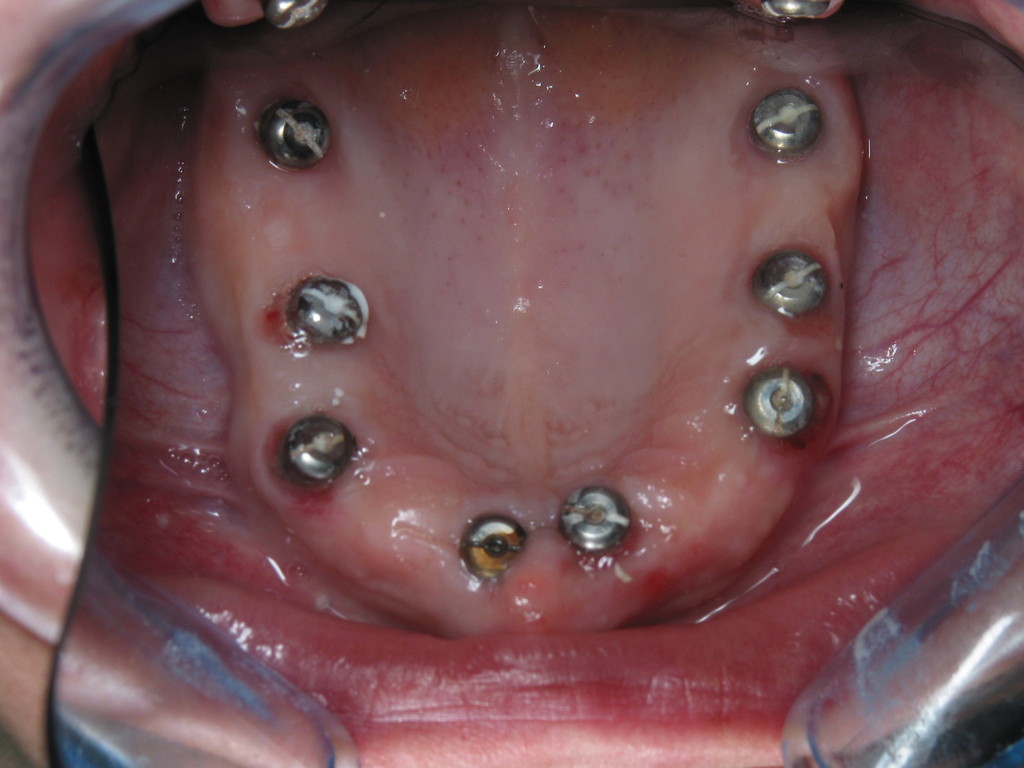

Paciente afectada de Enfermedad Periodontal Avanzada, en ambos maxilares.

En el maxilar superior, perdida ósea vertical generalizada de más de 5 mm, movilidad grado I y grado II.

En maxilar inferior , enfermedad periodontal avanzada del adulto, con perdida de inserción ósea y ligamentosade 5 mm en casi todas las piezas  a excepción de las piezas31 y 41 incisivos  inferiores, con recesisón gingival de atkins y sullivans grado 2.Con defecto vertical superior a 7 mm.